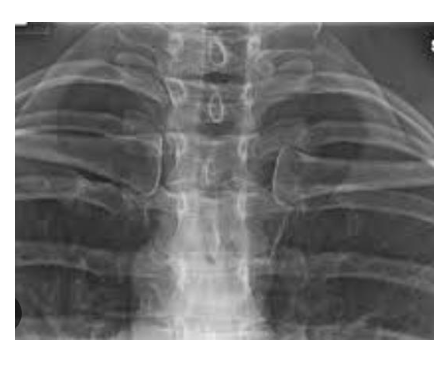

Identify the structure ? View?

Postero-Anterior, Chest